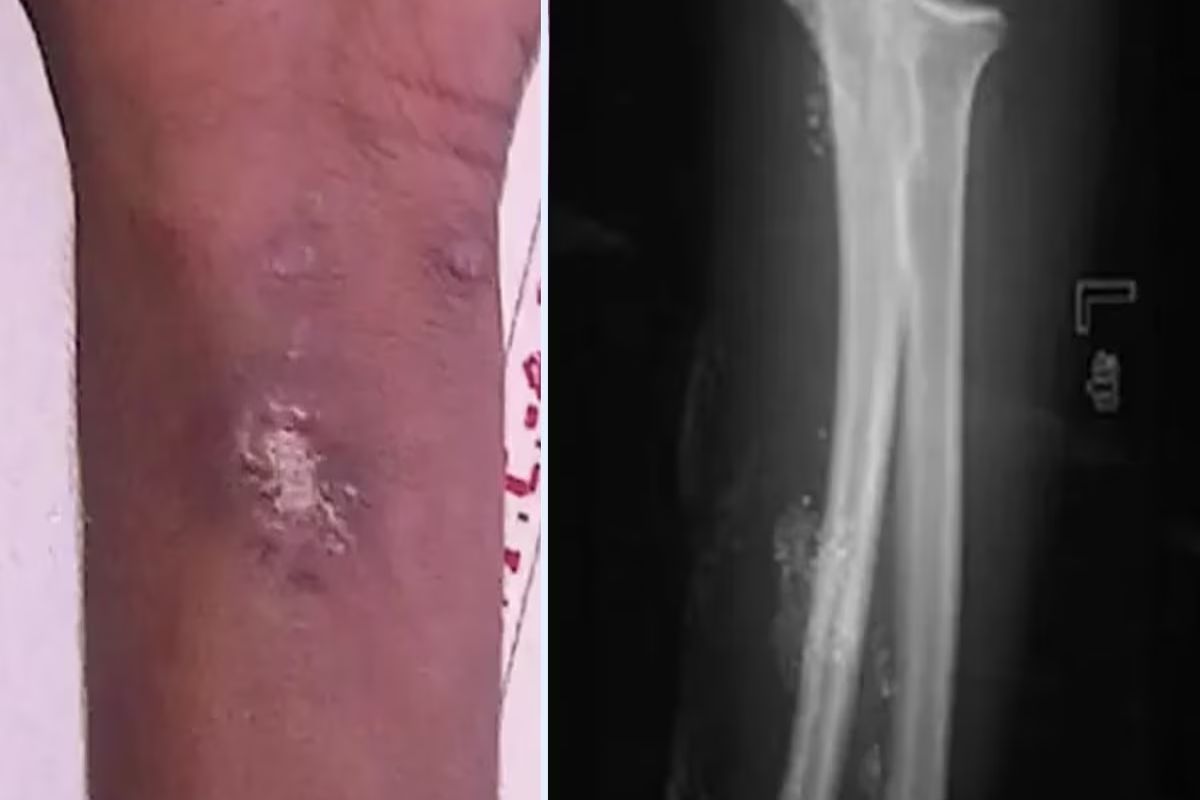

15 वर्षाचा मुलगा 2 वर्षापासून स्वतःला इंजेक्शन देत होता. तो स्पायडर मॅन बनू शकेल या आशेने तो स्पायडरलाही स्वतःला चावून देत होता. नॅशनल सेंटर फॉर बायोटेक्नॉलॉजी इन्फॉर्मेशनच्या अहवालात त्याने जाणूनबुजून शरीरात इंजेक्शन टोचल्याचं सांगितलं. मुलगा भारतातील ट्रॉमा सेंटरमध्ये गेला होता, जिथे डॉक्टरांना मुलाच्या डाव्या मनगटावर अनेक न बरे होणारे अल्सर आढळले. त्याने मर्क्युरी इंजेक्शन घेतले होते. हेही वाचा - shocking step : बायकोने दारु पिण्यापासून थांबवले, रागाच्या भरात नवऱ्याचं धक्कादायक पाऊल इंजेक्शन घेण्यामागे काही मानसिक समस्या असल्याचा संशय डॉक्टरांना होता. त्यावर मुलाने आपण जाणूनबुजून पारा टोचून घेतल्याचा खुलासा केला. अहवालात असे म्हटले आहे की हा मुलगा एक्स-मेनच्या मर्करी या पात्रापासून प्रेरित होता. डॉक्टरांनी सांगितले की त्याला कोणतीही मानसिक समस्या नाही आणि तिचा IQ सामान्य आहे. मुलावर शस्त्रक्रिया करण्यात आली आणि शस्त्रक्रियेनंतर तो बरा झाला. मुलांवर देखरेख ठेवली पाहिजे आणि मुलांनी घरी असे करण्याचा प्रयत्न करू नये याची काळजी पालकांनी घेतली पाहिजे. दरम्यान, आजकाल चित्रपट पाहून लहान मुलं तसंच करायला बघतात. कधी कधी ते स्वतःसोबतच खूप धक्कादायक करुन घेतात. ज्यातं त्यांनाही भान नसतं.